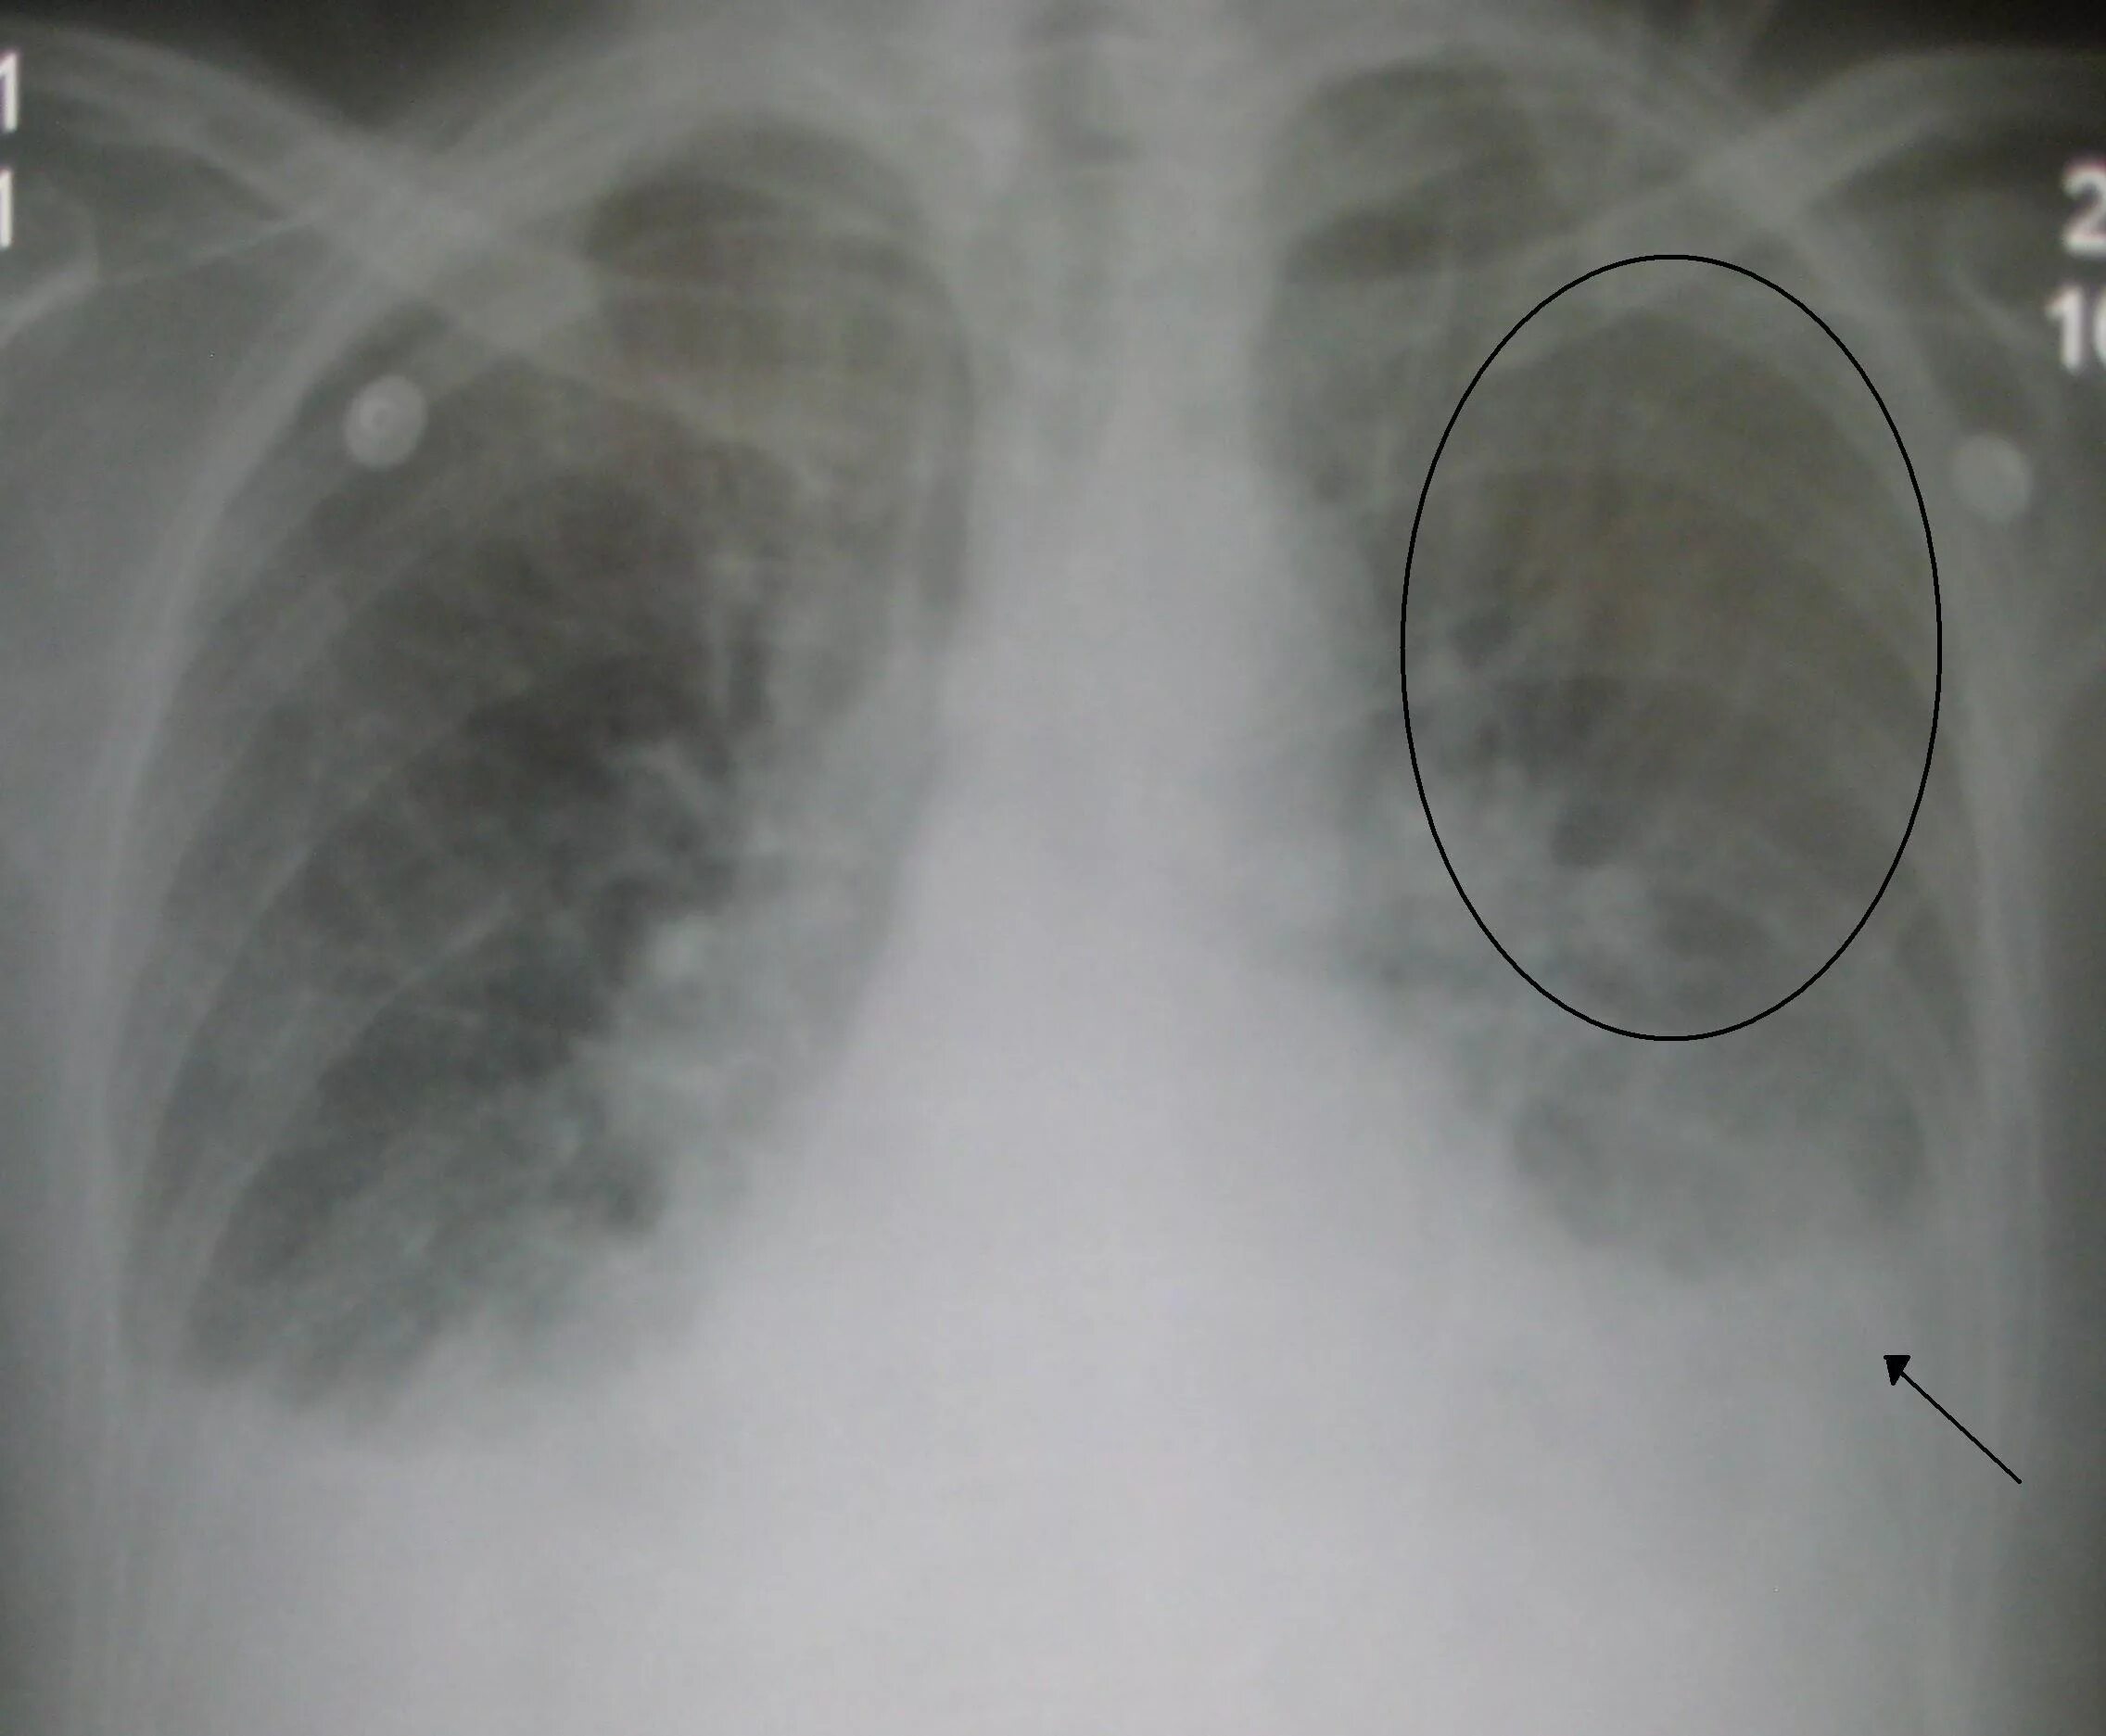

Отек легких причины у пожилых